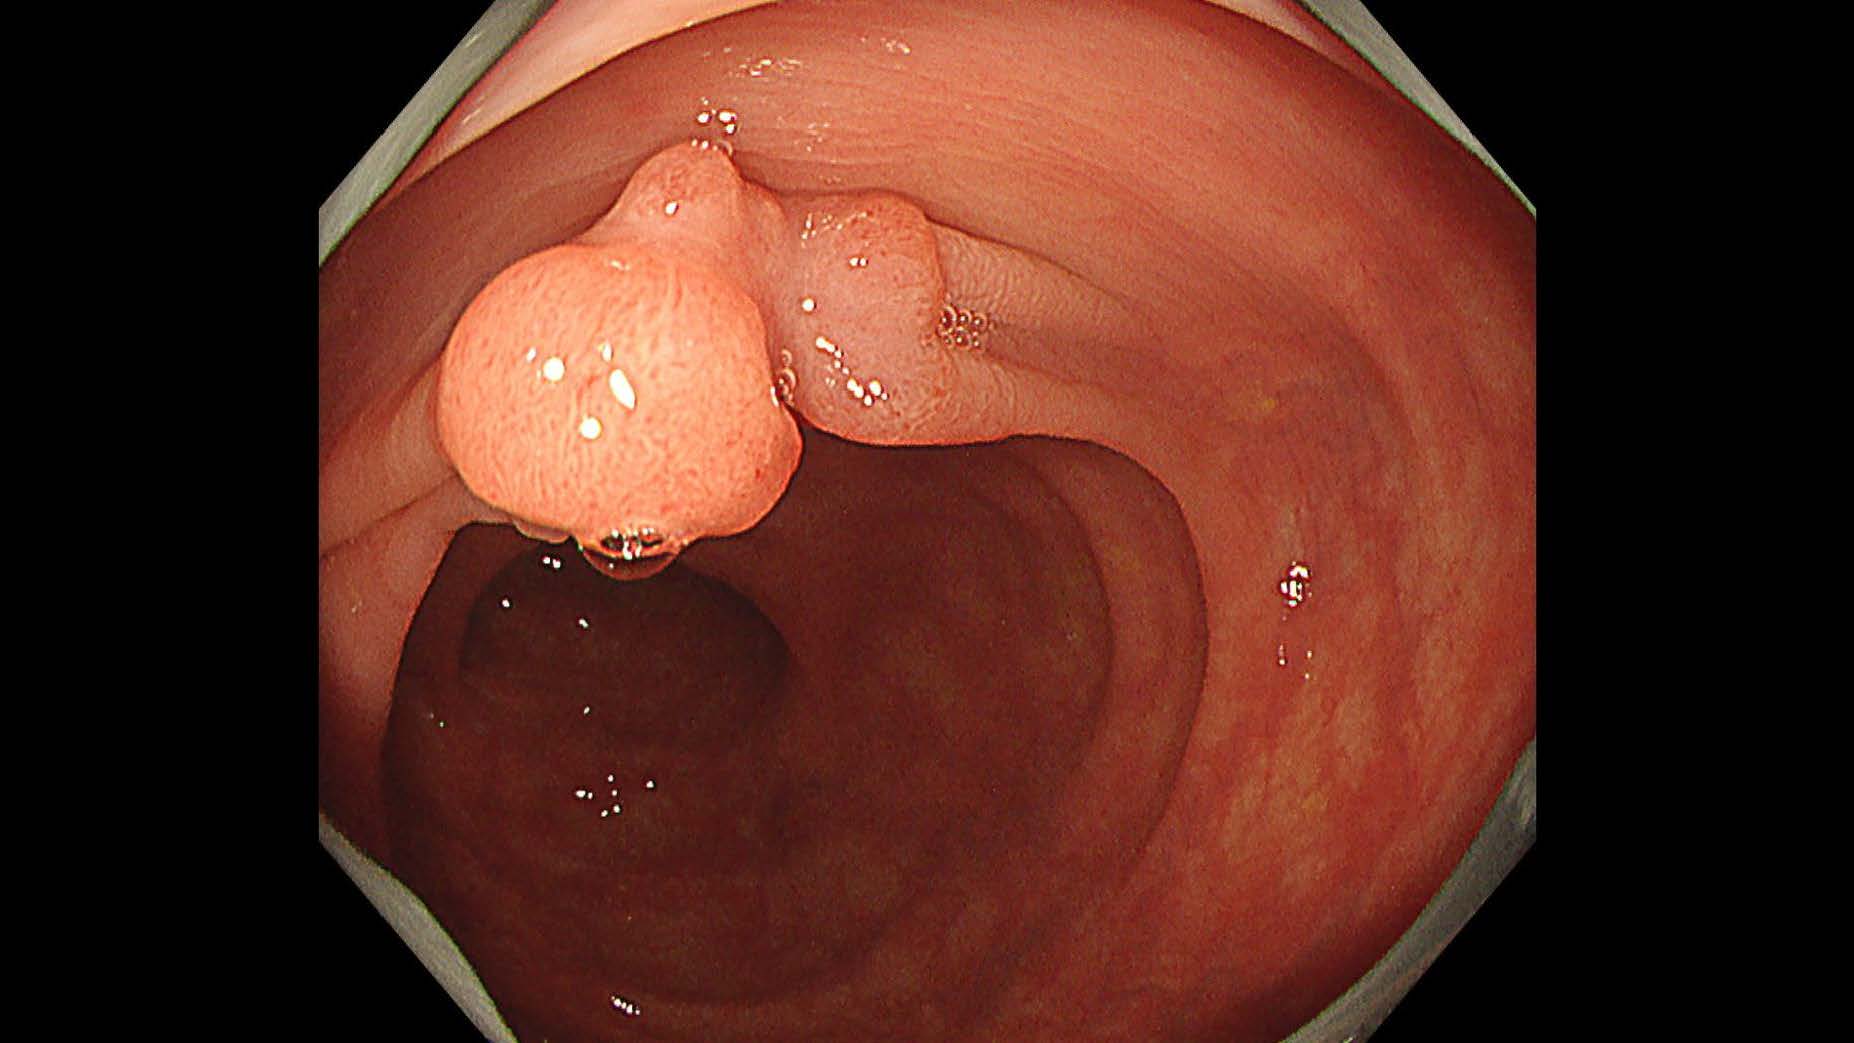

消化管Mapping~大腸~ 2025.6.11

消化管Mapping

消化管Mapping~大腸~

消化器内科

内視鏡検査・治療